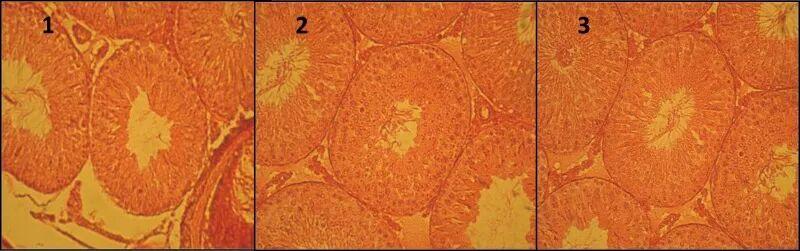

2015年2月發表在《Avicenna J Phytomed. 》的一篇研究表明,芹菜葉提取物,可以明顯改善精子發生過程,精子細胞數量有明顯改善,並且對某些精子生育參數改善也很有用。

2和3實驗組中,生精管直徑、睾丸體積以及精原細胞、初代精母細胞和精子的數量都有明顯提升,而且在高劑量實驗組(每公斤體重200毫克)中精子細胞數量增加更爲顯著。